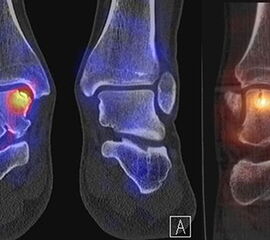

Abbildung 8.2. zeigt den Fall eines Patienten mit Verdacht auf ein knöchernes posteriores Impingement. Es bestanden Beschwerden dorsal bei Plantarflexion und ein Z. n. Distorsion des linken OSG vor 2,5 Jahren. Im MRT 2 Monate vor der SPECT/CT keine wegweisenden Befunde. Im SPECT/CT eindeutige fokal deutliche Mehrspeicherung im Bereich des Processus posterior tali.

Abbildung 8.3.a bis d demonstrieren Bilder einer Patientin mit Z. n. Arthrodese des linken OSG vor 6 Jahren. Das MRT ist bei ausgedehnten Metallartefakten nur bedingt aussagekräftig und weist nicht auf die auffälligen Befunde im SPECT/CT hin. Es bestehen sowohl fokale Stressreaktionen im Bereich eines Os trigonum und lateral im USG.